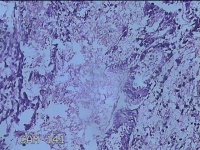

子宫腔内容物

性别

女

年龄

33岁

临床诊断

子宫内膜息肉?子宫异常出血

一般病史

阴道流血12天。

标本名称

大体所见

;纱布一块,内有灰白暗红色不规则碎组织3.5x2.8x1.3cm一堆。

图1